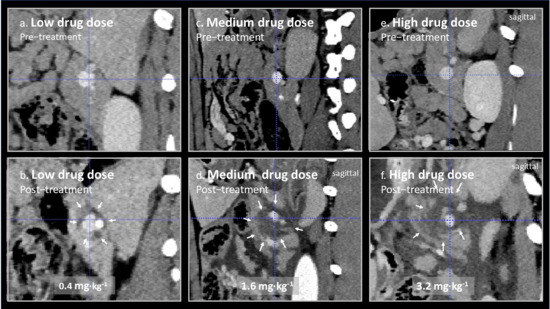

In Figure 2, representative images from treated splenic veins are shown in the plane perpendicular to the axis of the treated vein, below an image of the same area prior to treatment for animal 3 (low drug dose), 5 (medium drug dose), and 7 (high drug dose). Perivascular oedema was observed at all doses. In animal 3, it is doubtful weather there was any effect beyond oedema, but circumferential perivascular necrotic margins of increasing size were seen as the drug dose was increased.

Figure 2.

(a–f) Contrast-enhanced CT scans of treated splenic veins (blue dotted cross-hair) were taken before and 2 days after EPA. Areas of reduced uptake of contrast after treatment are marked by small arrows. The changes in animal 3 treated at a low Verteporfin dose of 0.4 mg∙kg−1 (a,b) are small, possibly perivascular oedema, and of questionable significance, but are of increasing size when the Verteporfin dose was increased to 1.6 mg∙kg−1 animal 5 (c,d) and 3.2 mg∙kg−1 (e,f), in animal 7. Lesions seen on CT were confirmed on histology to be due to pancreatic necrosis. The light dose was nearly constant for these three animals at 377, 311, and 321 J∙cm−1, for animals 3, 5, and 7, respectively (Table 1).